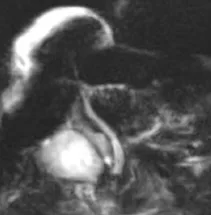

Figure 12.

A. Chez ce patient suivi pour une TIPMP de la tête du pancréas et ne présentant aucun argument clinico-biologique pour une pathologie biliaire, on pourrait discuter de discrètes « irrégularités » des VBIH : aspect en « collier de perles » (tête de flèche), sténose focale (flèche)… En réalité, il ne s’agit que de fausses images, banales en bili-IRM et simplement liées à la résolution spatiale et au rapport signal sur bruit limités : ici les VBIH sont normales.

B. Chez cet autre patient, il existe cette fois-ci des signes objectifs d’atteinte des VBIH : on note de multiples images de « disparition » segmentaire de voies biliaires, associées à une trop bonne visibilité en amont. Il s’agit d’un aspect typique de cholangite sclérosante primitive